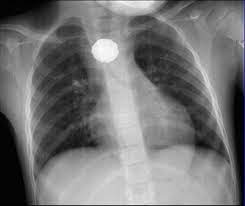

A través de una radiografía de tórax, el nuevo médico que atendió al nene encontró lo que le sucedía. “Les vi poner mirada extraña”, recordó la mamá de Luke y, al ver las imágenes, comenzaron a preguntar si existía la posibilidad que el se haya tragado una moneda o un botón.

De inmediato, lo trasladaron de urgencia a un hospital para determinar de qué se trataba el objeto que veían en los estudios. Según explicó la mamá, los profesionales decían: “No hay forma de que sea una pila porque comienzan a corroerse en tan solo dos horas”

En esta misma línea, Erica la mamá señaló: “Dijeron que tenía algo plateado en el pecho, pero que sería peligroso sacar ese objeto sin una cirugía completa”. De esta manera, se llevó adelante la intervención quirúrgica correspondiente y encontraron que la pila estaba envuelta en una cinta aislante, lo que permitió que no se degrade y le salvó la vida al menor de edad.